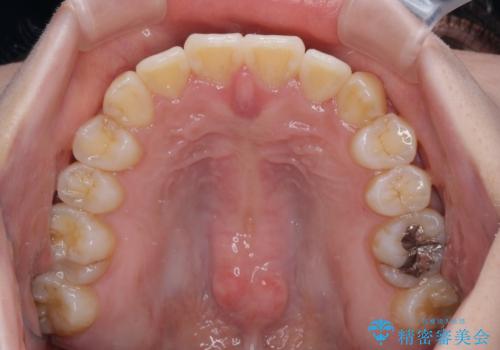

- 八重歯や前歯の捻転とクロスバイトが気になり、インビザラインによる矯正治療を希望して来院された患者様です。

上顎側切歯(上の真ん中から2番目の歯)が舌側転位している場合、無理して動かそうとすると歯髄壊死を起こすリスクが高い印象があります。

インビザライン単体でも治療は可能ですが、安全策としてインビザラインで歯列を移動する前に上顎前歯をワイヤー矯正で整え、その後上下歯列をインビザラインにて矯正治療を行うこととしました。

舌側転位している側切歯特有の、切縁の位置が不揃いであったり、根元が内側に引っ込んだ状態であったりという、インビザライン独特の仕上がりになることなく、きれいに整った歯列とすることができました。